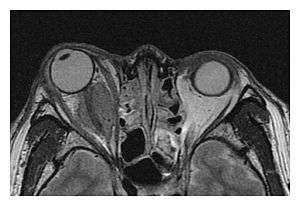

The extent of inflammation that can occur in IgG4-ROD is well demonstrated on magnetic resonance imaging (MRI).

![]() Enlargements in the left inferior rectus muscle and infraorbital nerve (arrow) in a 65-year-old man with a serum IgG4 of 404 mg/dL.[1] (T2-weighted MRI) |